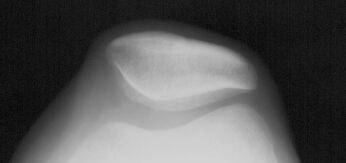

На боковом снимке профиль надколенника имеет две задние линии. Одна из них соответствует гребню надколенника, другая, более плотная, соответствует его наружному краю. Расстояние между этими двумя линиями и является надколенниковым индексом, который в норме составляет 5 мм (рис. 4). Значения ниже или равные 2 мм говорят в пользу нестабильности, которая, однако, может быть транзиторной, исчезающей при более сильном сгибании, чем на 15 или 30°.

Рисунок 4. Надколенниковый индекс. Объяснения в тексте.

Преимущество бокового снимка, по сравнению с аксиальными проекциями, связано с возможностью анализа движения надколенника в самом начале сгибания от 0 до 30°, когда он начинает внедряться в трохлеарное устье дистального эпифиза бедренной кости. В этот момент можно оценить глубину межмыщелковой борозды и установить дисплазию трохлеи, которая может оказаться причиной нестабильности.